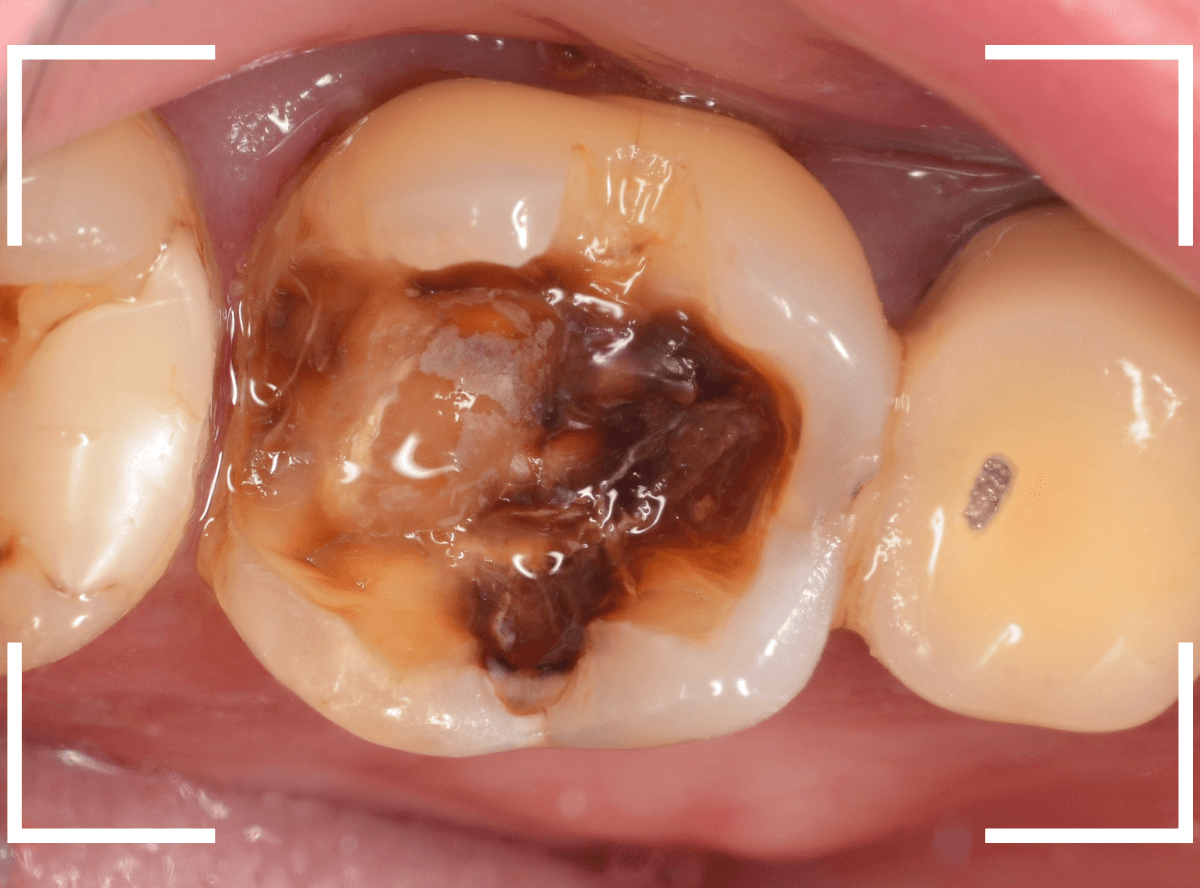

Case.10 レントゲンに写らない側面の虫歯を、少しずつ削って調べる

こちらも、虫歯が歯のあちこちで進行してしまっている患者さんのケースです。

特に側面の虫歯が深そうです。

側面にできた虫歯はレントゲン写真では診断しづらくやっかいです。

今回は「見るからに深そう」ですが。

さすがにレントゲン写真でも虫歯がありそうな事は確認できますが、実際にどうなってるのかはあまりはっきりわかりません。

少しずつ虫歯を除去していきます。

歯の側面から、手前の歯までつながった虫歯になっていました。

手前の歯までの虫歯を除去しました。

歯の後ろ側の側面も、大きな虫歯になっていますので、処置します。

隣の歯との間(隣接面)は、中で虫歯が広く進んでることが多いです。

結局、前後の歯に渡る広い虫歯でした。

レントゲン写真だけでは、ここまでの虫歯は判断できませんでした。